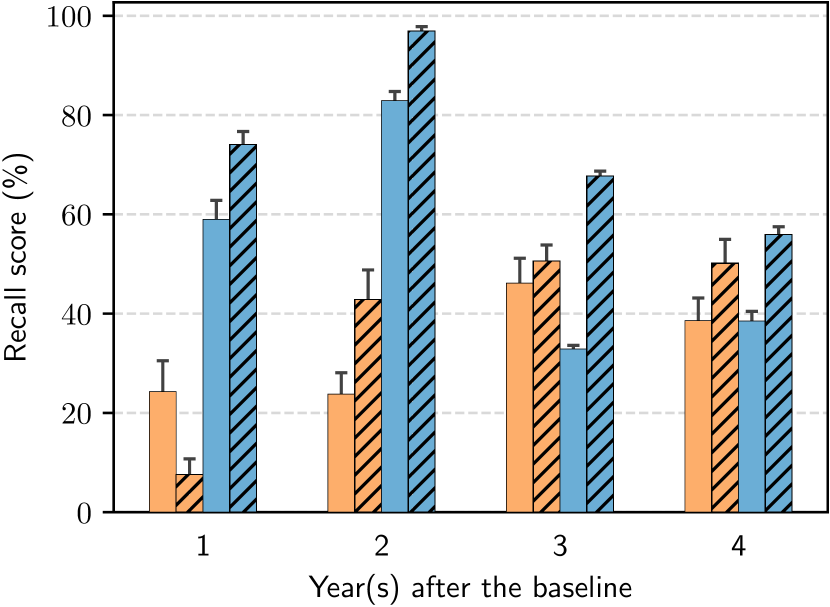

To provide additional insights, we further present the corresponding fine-grained results in Figure 5. Most of the time, patient-level models reduced the standard error in BA and RC of both CLIMATv2 and our RL-based agent. Particularly, at the 1-year time point, our patient-level policy exceeded the patient-level CLIMATv2 with the highest difference by approximately 15% in BA and 60% in RC. Furthermore, the greatest gap between patient-level and knee-level of our method occurred 3 years after baseline by approximately 20% in BA and 40% in RC. In general, our patient-level policy showed substantial improvement compared to other methods most of the time.

| Method | Year(s) | BA(%) | RC(%) | |

| Knee-level | CLIMATv2 | 1 | 57.09 1.69 | 24.29 6.22 |

| 2 | 50.87 1.26 | 23.77 4.30 | ||

| 3 | 56.34 0.84 | 46.15 5.00 | ||

| 4 | 55.60 1.16 | 38.59 4.55 | ||

| Ours | 1 | 60.43 0.72 | 58.98 3.84 | |

| 2 | 59.26 0.57 | 82.92 1.83 | ||

| 3 | 47.30 0.80 | 32.88 0.72 | ||

| 4 | 59.41 0.73 | 38.51 1.95 | ||

| Patient-level | CLIMATv2 | 1 | 51.83 0.77 | 7.55 3.18 |

| 2 | 56.71 0.95 | 42.83 5.97 | ||

| 3 | 58.73 0.79 | 50.58 3.24 | ||

| 4 | 58.38 0.89 | 50.16 4.80 | ||

| Ours | 1 | 62.81 0.57 | 74.08 2.62 | |

| 2 | 53.56 0.44 | 96.98 0.85 | ||

| 3 | 60.40 0.67 | 67.69 1.03 | ||

| 4 | 64.55 0.74 | 55.94 1.56 |